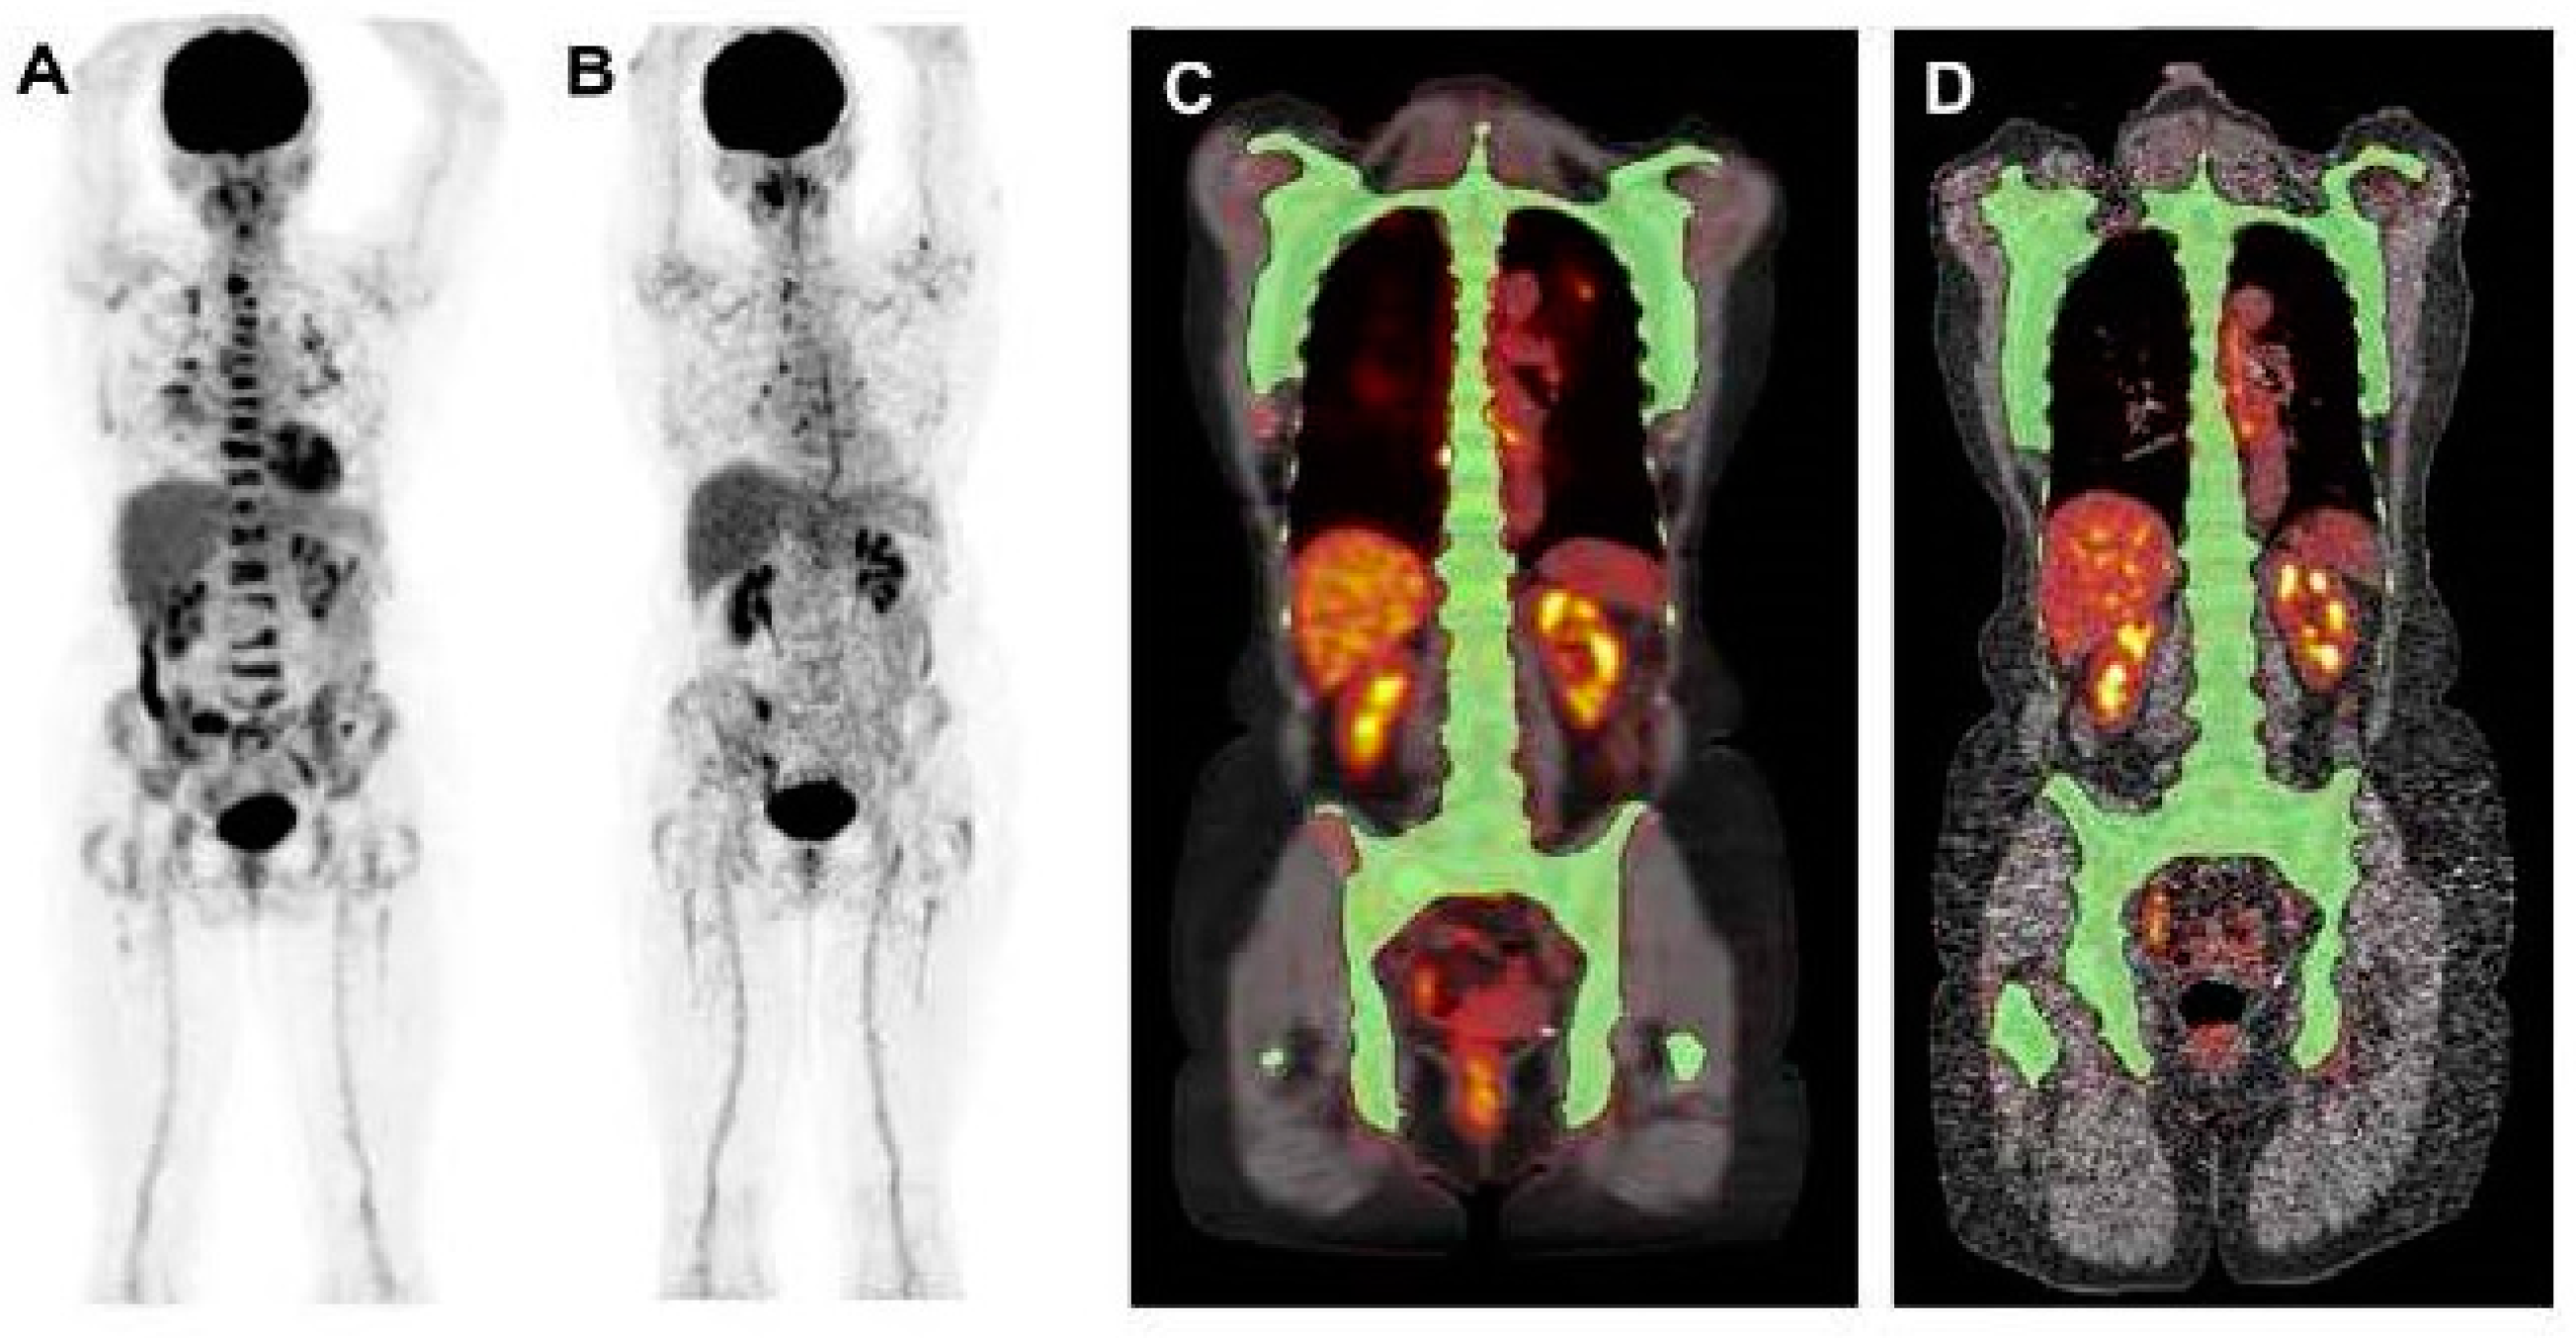

Evaluating the response to treatment is a significant area where [18F]FDG PET/CT might offer greater utility compared to conventional imaging methods [23] (Figure 4 and Figure 5). By analyzing the metabolic behavior in areas with clonal plasma cell growth, [18F]FDG PET/CT can precisely gauge and quantitatively measure alterations in cancer cell activity following therapeutic interventions [24,25,26,27,28,29]. Furthermore, there is a robust correlation between negative [18F]FDG PET/CT results and a highly positive response to treatment in myeloma patients [20].

Figure 4.

This figure presents the case of a 39-year-old patient with symptomatic multiple myeloma (MM) who was being prepared for high-dose therapy (HDT) and autologous stem cell transplantation (ASCT). This patient underwent an [18F]FDG PET/CT scan both before and after treatment. The maximum intensity projection (MIP) of the [18F]FDG PET/CT scan before treatment (A) revealed a combination of intense, widespread uptake in the axial skeleton and multiple focal bone marrow lesions in locations such as the sternum, ribs, humerus, scapula, and femur (indicated by arrows). The follow-up [18F]FDG PET/CT MIP after HDT and ASCT (B) demonstrated a complete remission of both the diffuse bone marrow uptake and the focal MM lesions. Figure 2, PMID: 31905752, PMCID: PMC6982887, OPEN ACCESS.

Figure 5.

This figure is displaying the baseline (A,B) and follow-up (C,D) [18F]FDG PET images of a patient with MM before high-dose chemotherapy and 2 months post-treatment. The [18F]FDG uptake by the lesions was quantified using an adaptive thresholding algorithm. The image was sourced from PMID: 31084773 (Figure 3), and permission was granted for its use.